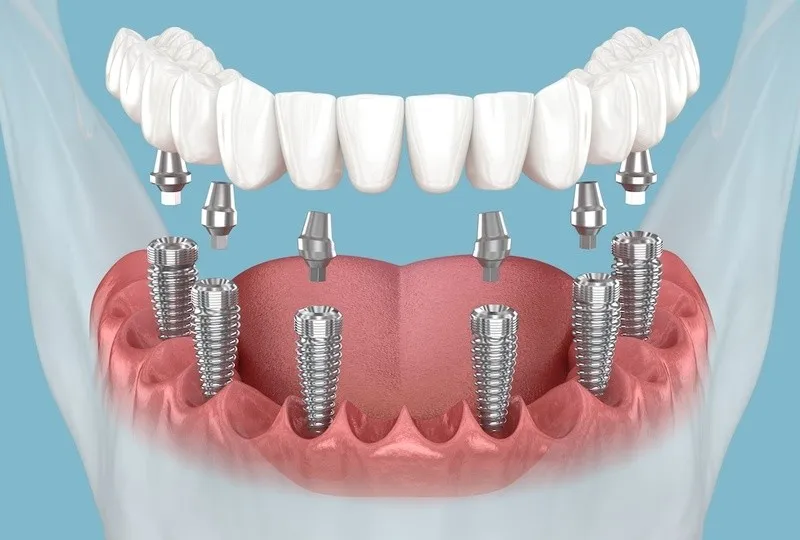

- Tái tạo Toàn hàm trên nền xương kém: Phục hình toàn bộ hàm (All-on-4/6) khi bệnh nhân mất răng lâu năm và có dấu hiệu tiêu xương nặng.

Implant Xương gò má (Zygoma Implant): Giải pháp dành cho bệnh nhân mất xương hàm trên trầm trọng, không thể thực hiện nâng xoang hoặc ghép xương. Trụ Implant được cắm vào xương gò má chắc khỏe, bỏ qua phần xương hàm trên đã tiêu. Đây là một ca phẫu thuật lớn, đòi hỏi bác sĩ phải có kinh nghiệm sâu rộng về giải phẫu.